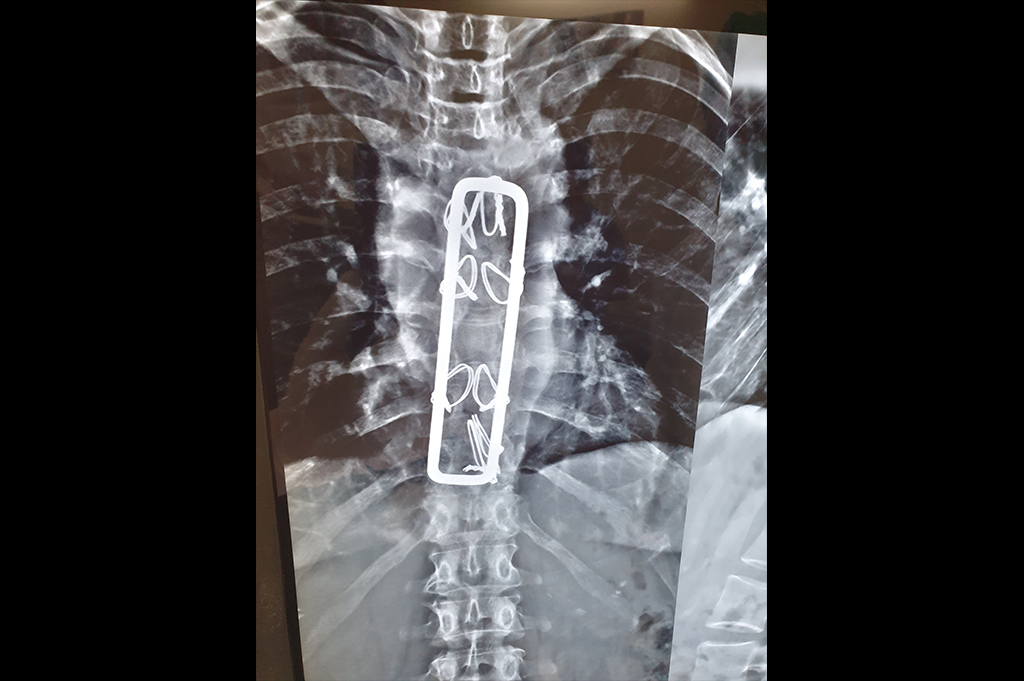

Spine